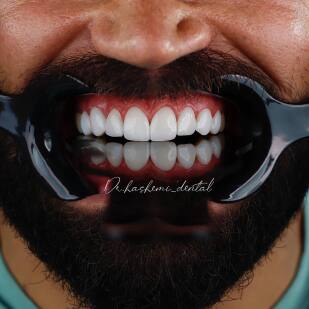

مرکز تخصص لمینت، کامپوزیت و ایمپلنت دندان در تهران

درمان های زیبایی دندان متنوع بوده، رایجترین درمانهای دندانپزشکی زیبایی عبارتند از سفید کردن دندان ها ، کامپوزیت دندان ، لمینت دندان ، روکش دندان ، ارتودنسی ، بریج و ایمپلنت

در مطب ما جدیترین و بروزترین تکنیک های دندانپزشکی به شما ارائه می شود.